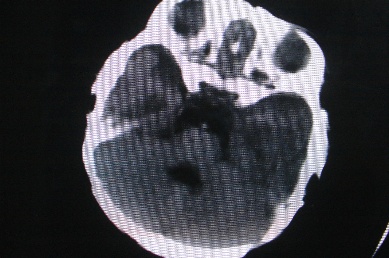

以下是引用余辉在2007-4-30 16:36:00的发言:[br]呵呵,图片不行啊,双肺弥漫斑片状影。右肺门增大,结构模糊。左侧脑室前部室管膜下可见团块状高密度影,周围有低密度环带,左额叶呈大片状低密度改变,略呈楔形,累及灰白质,局部脑沟裂消失,右额叶脑白质亦可见点状病灶(不知是伪影还是真病灶)脑室系统明显扩张,有全脑脑萎缩征象,不知其病史,暂考虑1双肺结核,左额叶结核性脑炎,(左侧脑室前部室管膜下肉芽?出血?)合并脑积水脑萎缩(左额叶低密度区不排除脑梗塞改变)2双肺非特异性炎症合并化脓性脑炎